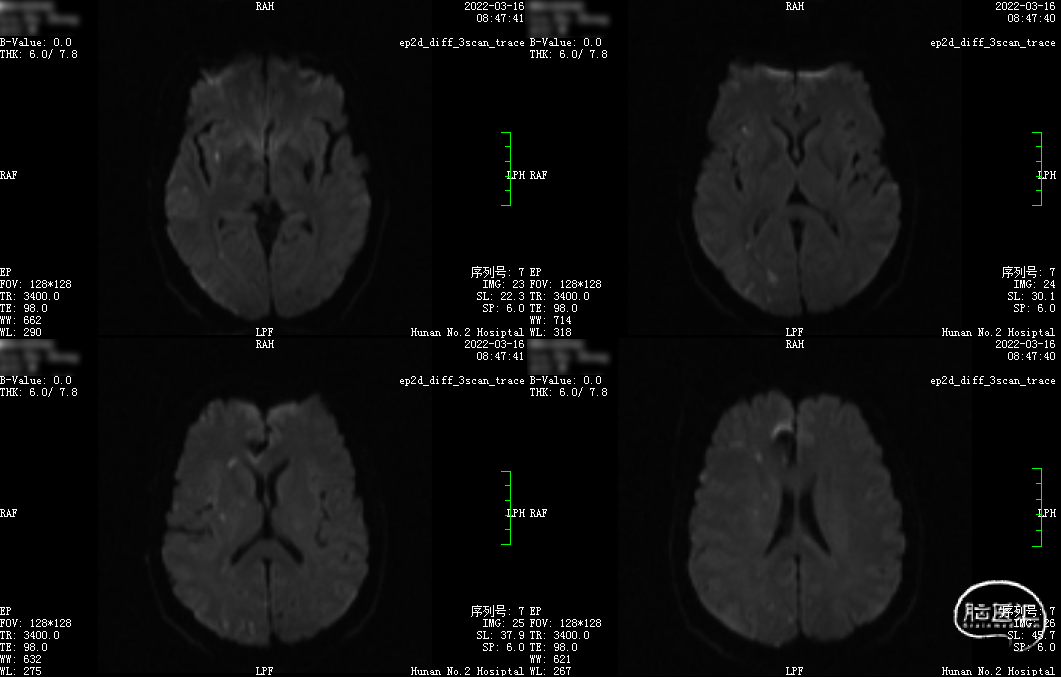

MRI(2022-03-10我院):

1.左侧脑室体部旁急性脑梗死;脑内多发腔梗及小缺血灶。2. 脑动脉硬化症,右侧大脑前动脉A3段动脉瘤,右侧大脑中动脉M1段分叉处动脉瘤可疑,建议CTA检查。

术后第一天,患者晨起醒后出现左上肢无力,查体:左上肢肌力1级,左下肢肌力5级,左上肢浅感觉减退。NIHSS评分:5分。予以急查CT示:1.右侧大脑前动脉、右侧大脑中动脉动脉瘤术后改变;2.左侧半卵圆中心、双侧基底节区腔梗同前。

术后复查MRI:右额、颞、顶、枕叶、右侧基底节区多发急性脑梗死。

头部MRA:颈内动脉、大脑前动脉、大脑中动脉通畅。